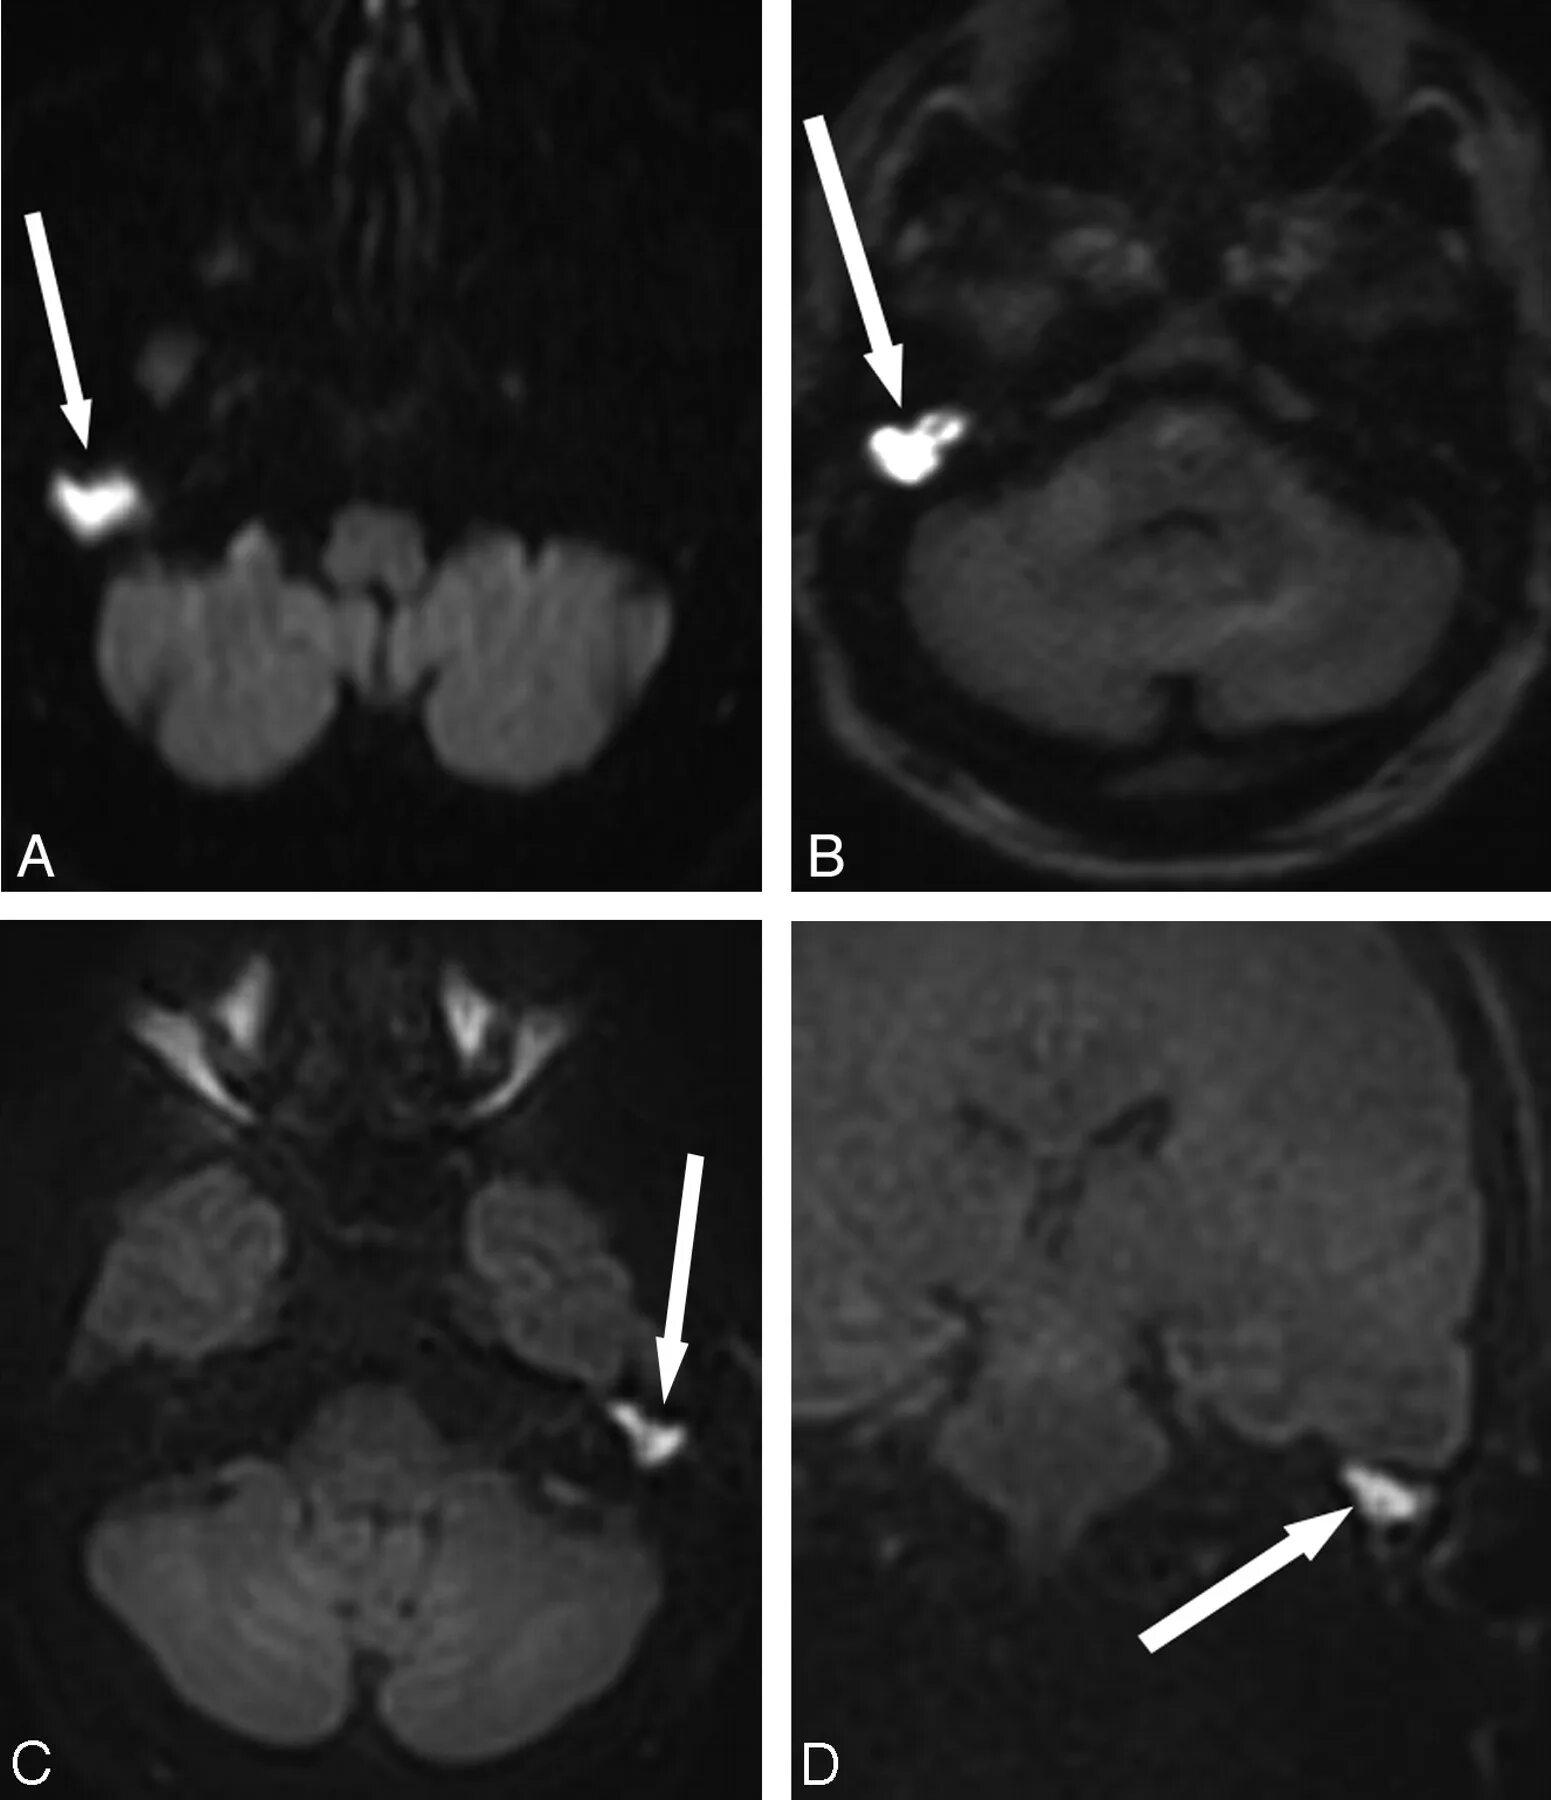

Мрт височных костей в режиме dwi